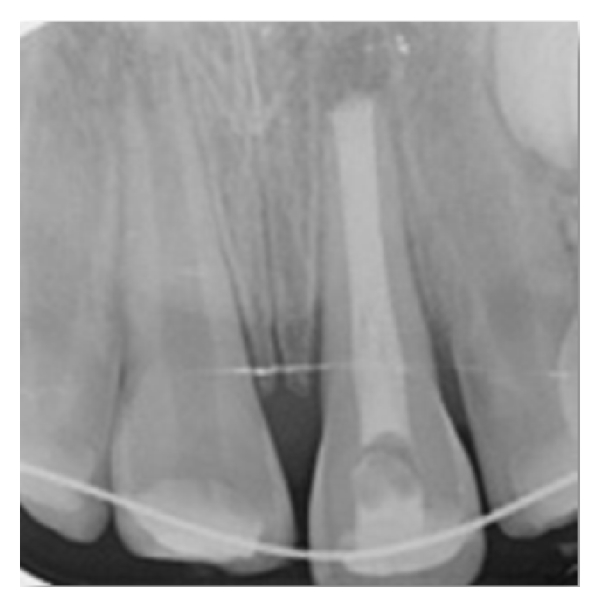

After informing the parents of the patient about possible risks, the socket of the tooth was gently rinsed with saline solution under local anesthesia (Maxicaine, Vem Drugs, Istanbul, Turkey). The root of the tooth was cleaned carefully to remove necrotic and dried remnants of periodontal tissue. Extra-oral endodontic treatment was carried out on the tooth, the root canals were filled with mineral trioxide aggregate (MTA) (BioAggregate, DiaDent, Burnaby, BC, Canada), and the tooth was replanted slowly, with slight digital pressure. Moist cotton pellet and glass ionomer cement (Ketac Molar, 3M/ESPE Dental Products, St. Paul, MN, USA) were used to restore the access cavity temporarily. The position of the replanted tooth was verified both clinically and radiographically. The tooth was stabilized using a flexible splint (0.195 inch round twist-flex arch wires, 3M Unitek, Monrovia, CA, USA) and the acid-etch composite resin technique (Clearfil Majesty Esthetic, Kuraray, Tokyo, Japan) (Figures 2 and 3). Moreover, oral hygiene instructions and advice about a soft diet and the need to use a chlorhexidine (Klorhex, Drogsan, Ankara, Turkey) mouth rinse during the stabilization period were provided at this time. Prophylactic antibiotic therapy with amoxicillin trihydrate/potassium clavulanate (Beecham Laboratories, Bristol, TN, USA) at a dose of 625 mg/day was prescribed for one week. The patient was also referred for an antitetanus booster. The parents were informed about the importance of regularly returning for clinical and radiographic follow-up. The patient was reviewed after two weeks, and no clinical or radiological pathological changes were detected. The patient was seen again four weeks after replantation, and the splinting wire was removed at this appointment. The permanent restoration of the fractured teeth crowns was completed with resin composite (Clearfil Majesty Esthetic, Kuraray Tokyo, Japan). In the third month follow-up, a percussion test of the avulsed tooth revealed a change in the percussion sound due to ankylosis. At a recall visit 12 months later, the right central incisor gave a negative response in a vitality test. An apexification procedure using calcium hydroxide (Sultan Chemists Inc., Englewood, NJ, USA) was started to induce apical closure. During an 18-month follow-up period, the replanted tooth remained in a stable, functional position but showed initial replacement resorption, ankylosis, and approximately 0.5 mm infraocclusion (Figures 4 and 5). The patient will be monitored till her growth is complete and appropriate treatment will be carried out if needed. CBCT images were taken to evaluate the relationship between the lateral incisor and permanent canine roots.

Two weeks after replantation, the patient was reviewed, and no clinical or radiological evidence of pathological changes was detected. The patient was seen again four weeks after replantation, and the splinting wire was removed at this appointment. The permanent restoration of the fractured teeth crowns were completed with composite resin. At a recall visit three months later, ankylosis of the replanted tooth was observed with a percussion test. Clinical and radiographic controls were performed at six and 12 months. During the 12-month follow-up, clinical and radiographic examinations showed satisfactory functional and esthetic values for the avulsed tooth but some initial resorption and ankylosis with no infraocclusion (Figures 9 and 10). The patient will be monitored till her growth is complete and appropriate treatment will be carried out if needed.